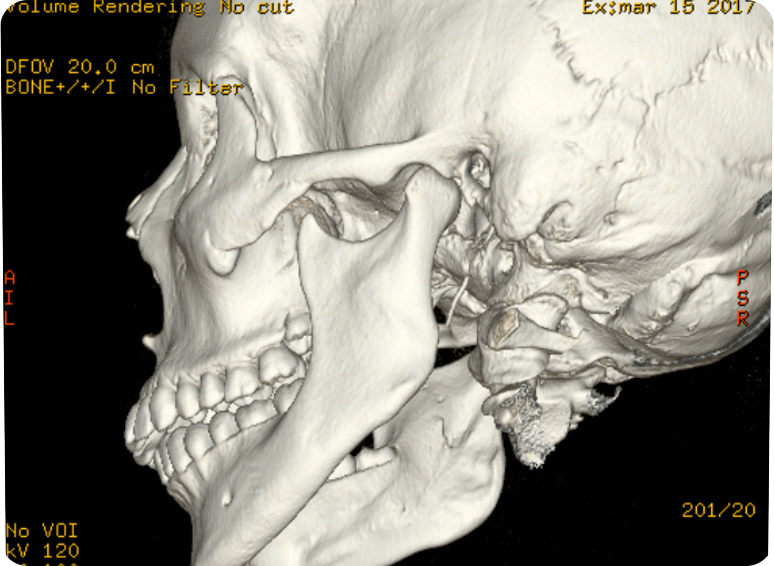

Mediante una tomografía logramos una imagen precisa para garantizar el diagnóstico.